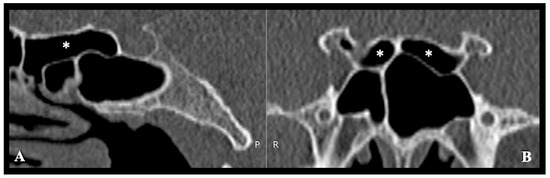

Background/Objectives: The aim of this study was to develop a novel Nasal Spine-Guided Classification for assessing the alveolar vertical extension of the maxillary sinus and to evaluate its anatomical relationship with the roots of the posterior teeth using CBCT in a Saudi [...] Read more.

Background/Objectives: The aim of this study was to develop a novel Nasal Spine-Guided Classification for assessing the alveolar vertical extension of the maxillary sinus and to evaluate its anatomical relationship with the roots of the posterior teeth using CBCT in a Saudi subpopulation. Methods: Maxillary sinus pneumatization was measured using cone-beam computed tomography for 380 patients. The assessment was performed along a horizontal plane extending between anterior and posterior nasal spine. In addition, pneumatization was evaluated in edentulous areas, and between the roots of multi-rooted teeth. Maxillary sinus membrane thickness was also measured. The results were expressed as mean, median and interquartile range, and considered statistically significant at a p-value < 0.05. Results: The mean maxillary sinus pneumatization on the left side was 8.8 ± 4.32 mm, and 8.58 ± 4.85 mm on the right side, with no statistically significant difference. The median of pneumatization in the edentulous area and between the roots on left side were 5.1 and 3.8 mm respectively, while on the right side, the median pneumatization was 5.03 and 3.04 mm. In addition, the proximity of the maxillary root apices to the sinus floor revealed a zero distance in 80.49% of the roots on the left side and in 79.48% on the right side. Furthermore, the results indicated no statistically significant association between maxillary sinus membrane thickness and pneumatization in the edentulous area. Conclusions: CBCT analysis revealed a predominance of advanced maxillary sinus pneumatization (Class III) and a high frequency of direct contact between posterior maxillary root apices and the sinus floor in the studied population. Additionally, no significant association was identified between maxillary sinus membrane thickness and sinus pneumatization in edentulous areas. Full article

Figure 1